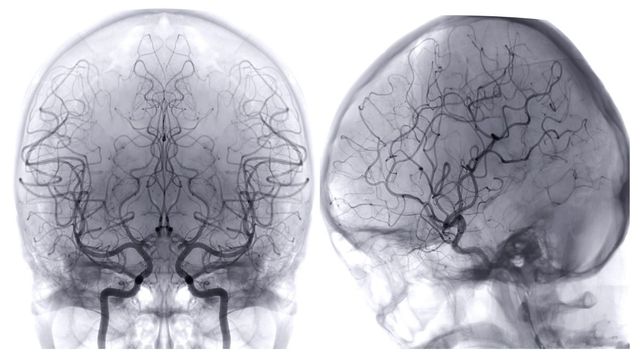

기사의 이해를 돕기 위한 이미지. / Radiological imaging-shutterstock.com